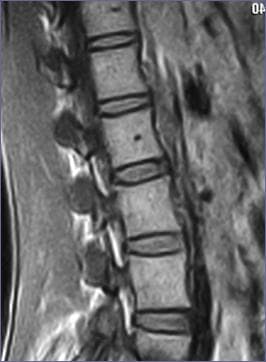

Анатомія хребця

Анатомічно кожен хребець представляє собою кісткове утворення, в якому виділяється три основні структури:

тіло хребця (1), що приймає на себе основне осьове навантаження, суглобові відростки (2), що забезпечують рухи в усіх площинах, поперечні (3) і остисті (4) відростки, до яких прикріплюються м'язи, що здійснюють ці рухи. Спинний мозок разом з нервовими корінцями, що виходять з нього, оточений з усіх боків твердою мозковою оболонкою, проходить через весь хребтовий стовп у так званому, хребтовому каналі (5). Останній обмежений спереду заднім краєм тіла хребця, по боках – суглобовими відростками, ззаду – остистими відростками та дугами, що відходять від них.